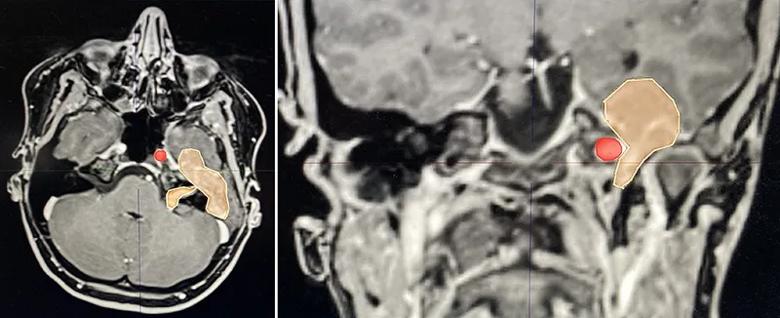

Eventually the patient did develop new facial nerve weakness and began experiencing headaches. Her MRI in December 2023 revealed significant tumor growth to the point that it was approaching the brain stem (Figure 1). “The growth was at such a clip that it was clearly time to start planning the resection surgery,” Dr. Recinos notes.

MRIs of the head showing a tumor

Figure 1. MRIs from December 2023, eight months before tumor resection. The peach-colored region is the tumor, located in the middle cranial fossa and extending into the internal acoustic canal. Note the proximity to the carotid artery, shown by the red dot.